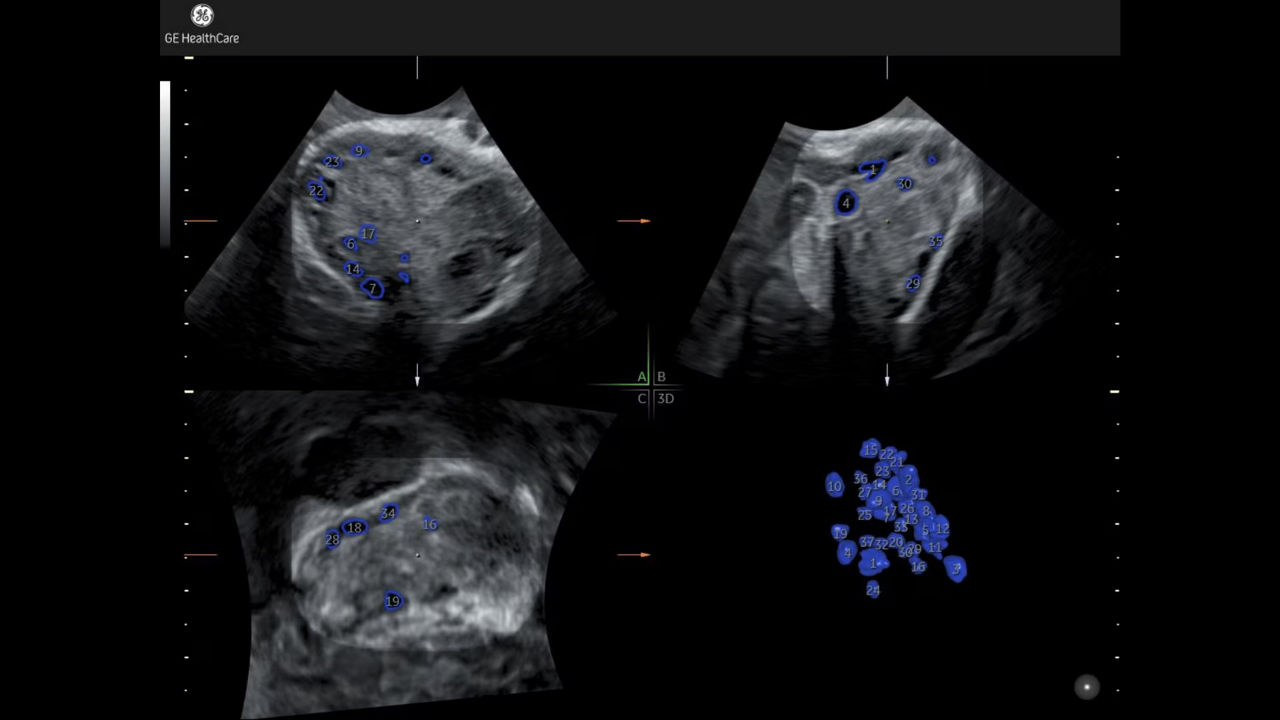

SonoAVC™antral

Simplifies assessment of ovarian reserve.

Developed by GE HealthCare - Voluson™

6_sonoavc-antral

SonoAVC™ follicle with Auto Caliper

Automate follicle counts in 2D or 3D

Developed by: GE HealthCare - Voluson™

1_sono-avc-follicle-with-auto-caliper